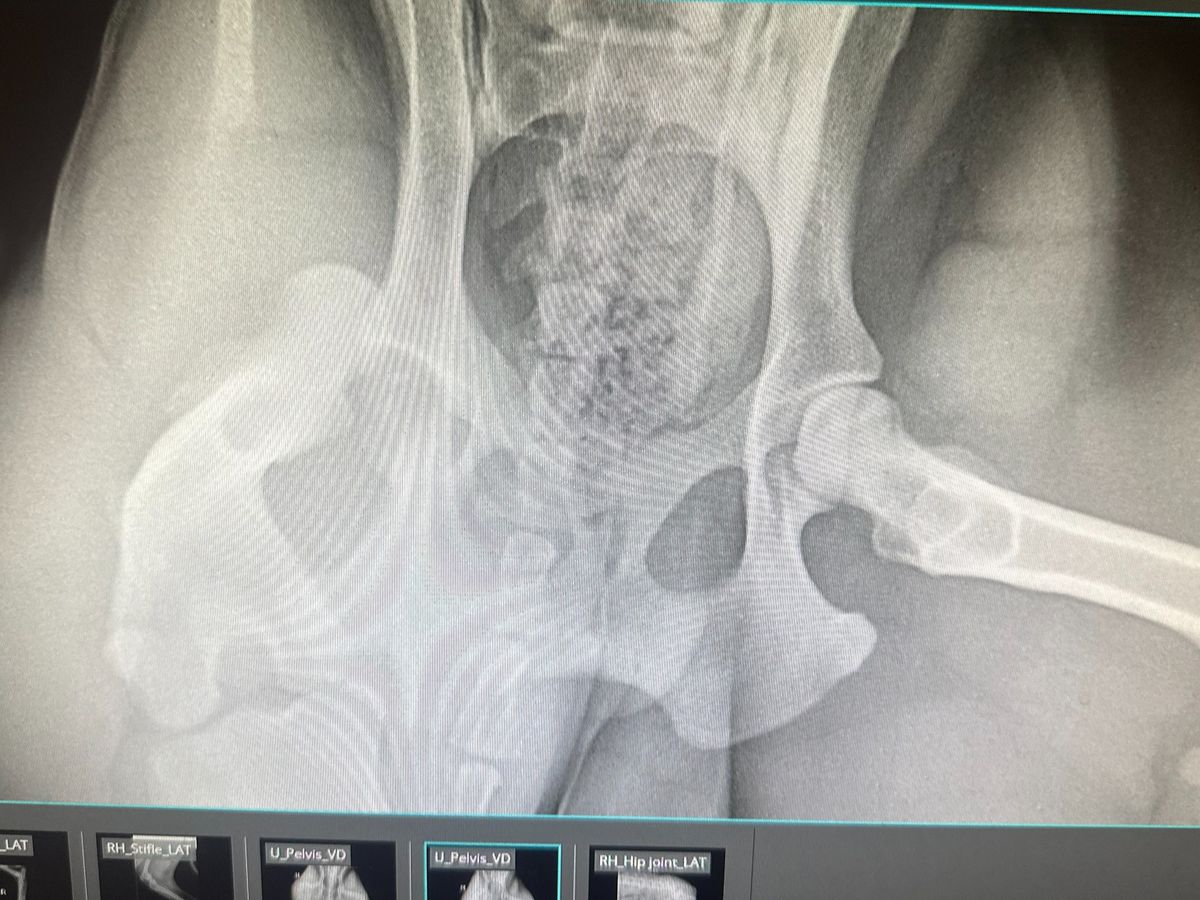

Hi my name is Cheraye, and my pupper Whiskey needs to have an FHO or pin and toggle surgery. He got into an accident and dislocated his hip. I hate to ask for help but we just do not have the funds. And we do not qualify for Carecredit or Scratch Pay. Please help if you can.. current price quotes are